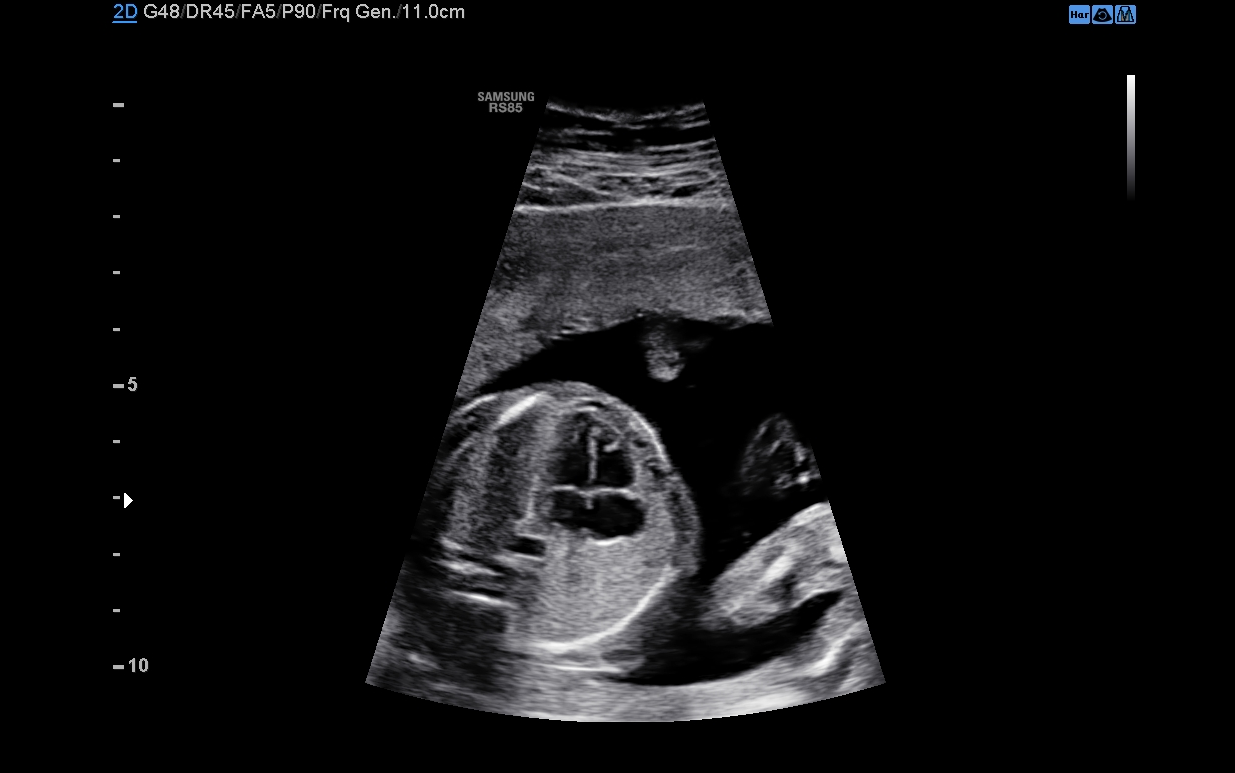

Uniformní zobrazení celé oblasti od blízkého po vzdálené pole

S-Harmonic ™ je nová harmonická technologie zlepšující čistotu obrazu od blízkého po vzdálené pole. S-Harmonic ™ snižuje šum signálu a poskytuje jednotnější ultrazvukové obrazy. V kombinaci s převodníky S-Vue ™ posouvá S-Harmonic ™ kvalitu obrazu RS80 EVO o krok dále.